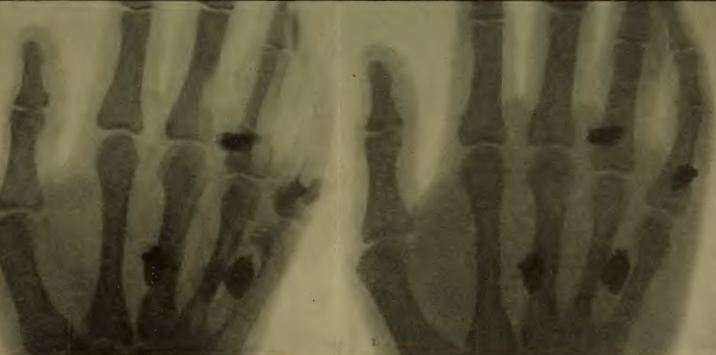

La radioscopie et la radiographie du corps humain fournissent des contrastes qui permettent de réaliser des images d'une grande beauté, avec de nombreux détails de structure (planche II).

EXAMEN DES FRACTURES.—On peut dire que les soins nécessités par les fractures d'os ont absorbé la plus grande partie du temps consacré aux blessés dans les hôpitaux. Non seulement ces fractures se sont produites en nombre considérable, mais de plus, elles ont été souvent très longues à atteindre un état de guérison plus ou moins complète et ont occasionné aux blessés des souffrances longues et souvent cruelles. Même quand elles offrent peu de gravité, qu'il n'y a ni esquille ni perte de matière osseuse, ni suppuration, la réparation qui se fait par soudure des fragments grâce à la formation d'os nouveau demande tout au moins plusieurs semaines. Après un repos suffisant, avec maintien de l'os fracturé dans la position dans laquelle il doit se consolider, il se forme un cal, région de soudure très parfaite dans les cas les plus favorables. Quand la fracture est grave, quand elle porte sur des os très importants, quand il y a eu broiement ou solution de continuité importante, la guérison est beaucoup plus longue et plus difficile. Ces terribles fractures dont on a tant vu pendant la guerre, comportent souvent de nombreuses esquilles qui entretiennent une suppuration persistante, et nécessitent des interventions de nettoyage. Les os, très profondément atteints, ne sont pas toujours en état de se reformer; la science chirurgicale réussit cependant à obtenir dans bien des cas des résultats merveilleux, par l'emploi de «greffes osseuses» qui facilitent la soudure en comblant les vides au moyen de portions d'os sain, et par l'application d'agrafes qui maintiennent en liaison les fragments d'os jusqu'à la réparation. Toutes ces fractures graves nécessitent des précautions spéciales pour que le cal tant souhaité se forme correctement, de manière à conserver aux fragments d'os une bonne position, et à ne point entraîner de déformations exagérées qui occasionnent des infirmités. La chirurgie dispose pour cela d'appareils spéciaux destinés à maintenir en position normale les os fracturés: gouttières, appareils plâtrés, etc.; elle emploie aussi des méthodes de travail telles que l'extension permanente, fréquemment pratiquée dans les fractures du fémur.

Dans toutes les phases de ces efforts laborieux pour obtenir la guérison dans les meilleures conditions possibles, et pour réparer dans une certaine mesure même ce qui paraît irréparable, le chirurgien a constamment recours aux rayons X, guide et conseil le plus parfait qu'il puisse avoir à sa disposition. Le blessé est généralement apporté sur un brancard dans la salle de radiologie et couché sur la table, au-dessous de laquelle se trouve l'ampoule à rayons X; l'écran radioscopique est placé sur le corps dans la région de la fracture. Le premier coup d'œil jeté sur la fracture à l'aide de l'écran radioscopique nous apprend sa gravité, son extension, le degré de délabrement, l'importance des esquilles, l'écart des os de la position normale. Cet aspect est généralement aussitôt fixé au moyen d'un dessein fait sur le verre qui recouvre l'écran et reporté ensuite par transparence sur un papier calque.

Pour avoir une opinion juste sur la direction des os, il est utile de faire deux calques dans des plans différents, par exemple une vue de face et une vue de profil, quand le déplacement du blessé est possible. Et même si la souffrance éprouvée par le malade ne permet pas un retournement, on peut encore dans bien des cas, obtenir un calque de profil, en plaçant l'ampoule au niveau du corps, latéralement, de manière à envoyer les rayons dans une direction horizontale, par exemple au travers d'une cuisse ou d'une jambe, de l'autre côté de laquelle l'écran est disposé verticalement. Si l'on a eu soin de bien centrer l'ampoule, pour opérer avec les rayons voisins du rayon normal, on se trouvera dans de bonnes conditions pour obtenir des images nettes et pour tracer des calques corrects.

Les calques obtenus sont conservés comme documents, et il y a lieu d'en prendre de temps en temps de nouveaux, soit pour suivre les progrès de la guérison, soit pour constater les résultats d'une intervention chirurgicale, destinée à nettoyer le foyer de fracture ou à rectifier la position des os. L'ensemble de ces calques reproduit l'histoire de la lésion, histoire parfois douloureuse, mais plus souvent réconfortante, car l'effort persévérant conduit à améliorer dans une large mesure des cas qui paraissent désespérés.

Le travail qui vient d'être décrit peut se faire par la radioscopie seule. Toutefois, la radiographie est d'un grand secours, et il est désirable de la pratiquer quand les conditions le permettent; elle est même, quelquefois, d'une véritable nécessité. Les plaques peuvent être prises dans les positions les plus favorables, reconnues à l'aide de la radioscopie; les dimensions des plaques peuvent donc être réduites au strict nécessaire. Le rayon normal passe en général par la région centrale de la plaque. L'image obtenue peut être examinée à loisir; elle offre des détails plus fins que ceux qu'il est possible de distinguer en radioscopie. Certaines fractures très fines, sans déplacement des fragments d'os, peuvent passer inaperçues pour l'observation radioscopique, mais apparaissent très nettement sur une bonne radiographie[1]. Celle-ci peut donc donner un complément d'information et, de plus, elle fournit, à partir des clichés négatifs, des tirages positifs, très supérieurs en perfection aux calques les mieux dessinés et, de plus, indépendants de l'interprétation du dessinateur.

Radiographie d'une jambe dans du plâtre. Fracture des deux os avec déplacement. A gauche: vue de face. A droite: vue de profil. — PLANCHE VI.

PLANCHE 7. — Radiographie d'un avant-bras. Fracture du radius avec perte de substance. A gauche: vue de face. A droite: vue de profil.

Les planches VI et VII reproduisent des radiographies de fractures suivant des documents originaux. On peut s'y rendre compte de la différence d'aspect d'images obtenues de face et de profil. Les planches VIII et IX représentent des fractures en voie de guérison, avec formation de cal.